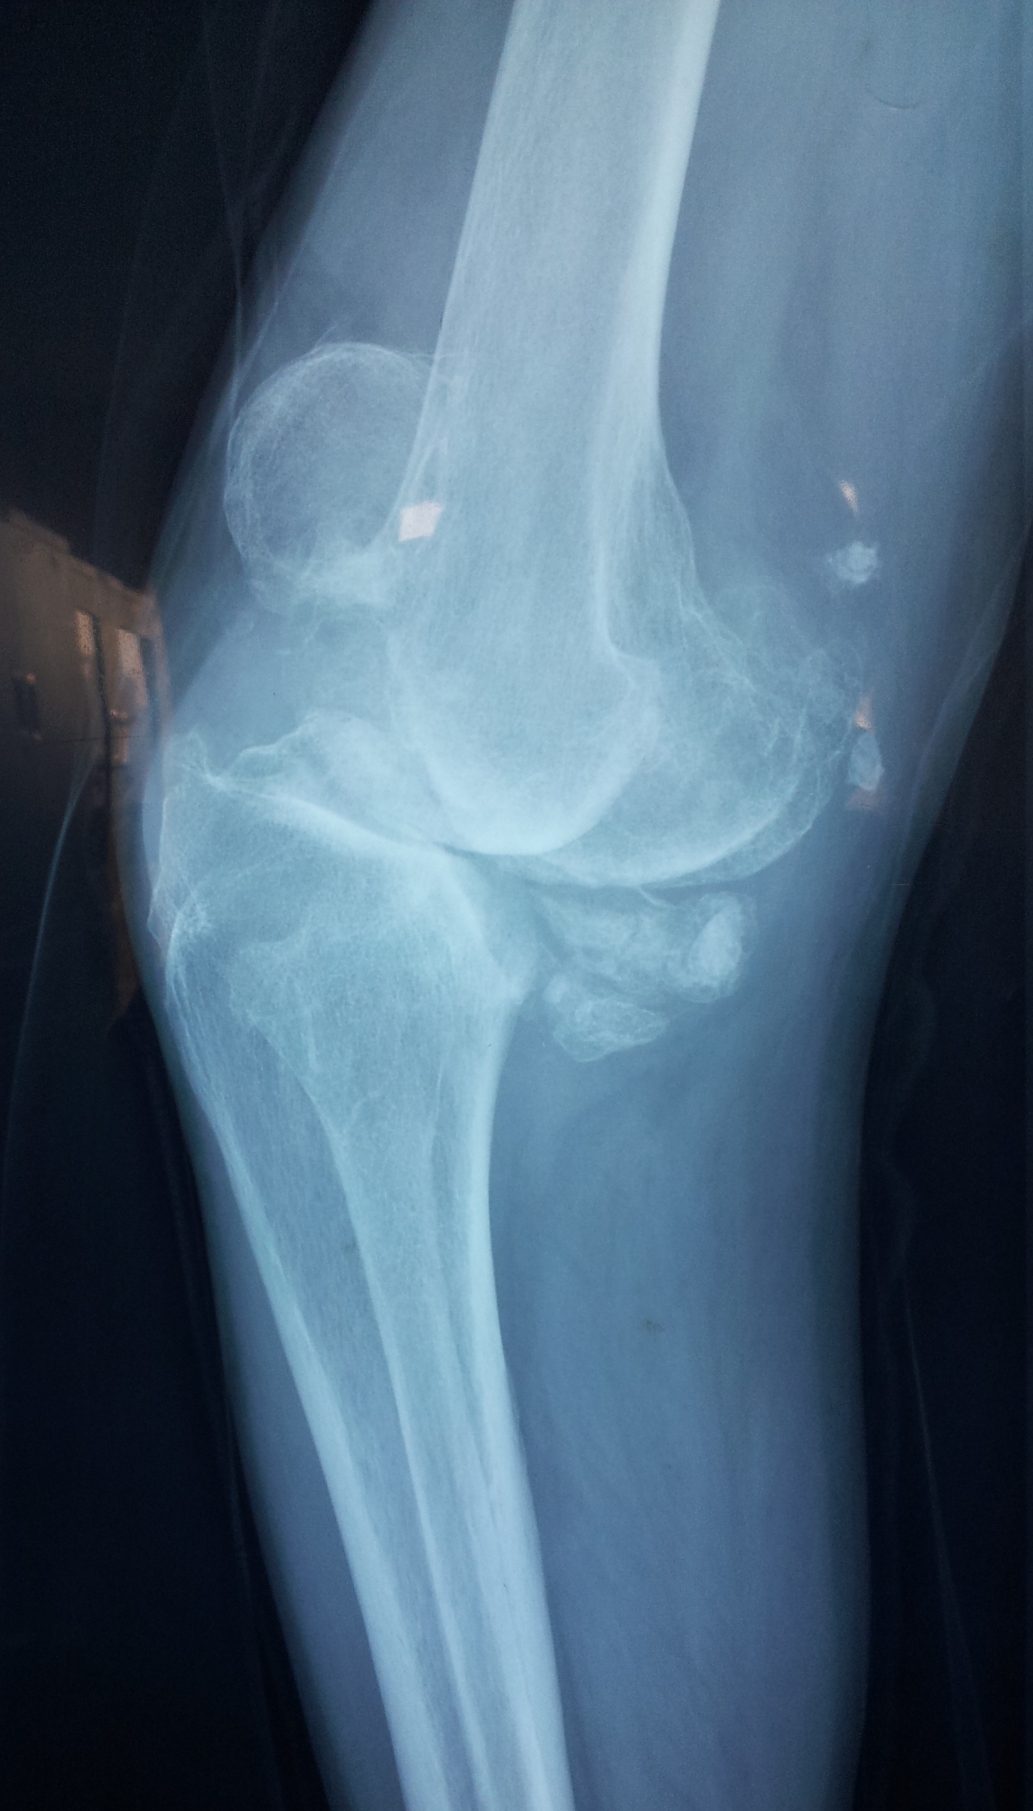

典型病例:患者,女,60岁,右膝骨性关节炎(重度内翻畸形)

术前                           术后

术前  侧位                         术后侧位